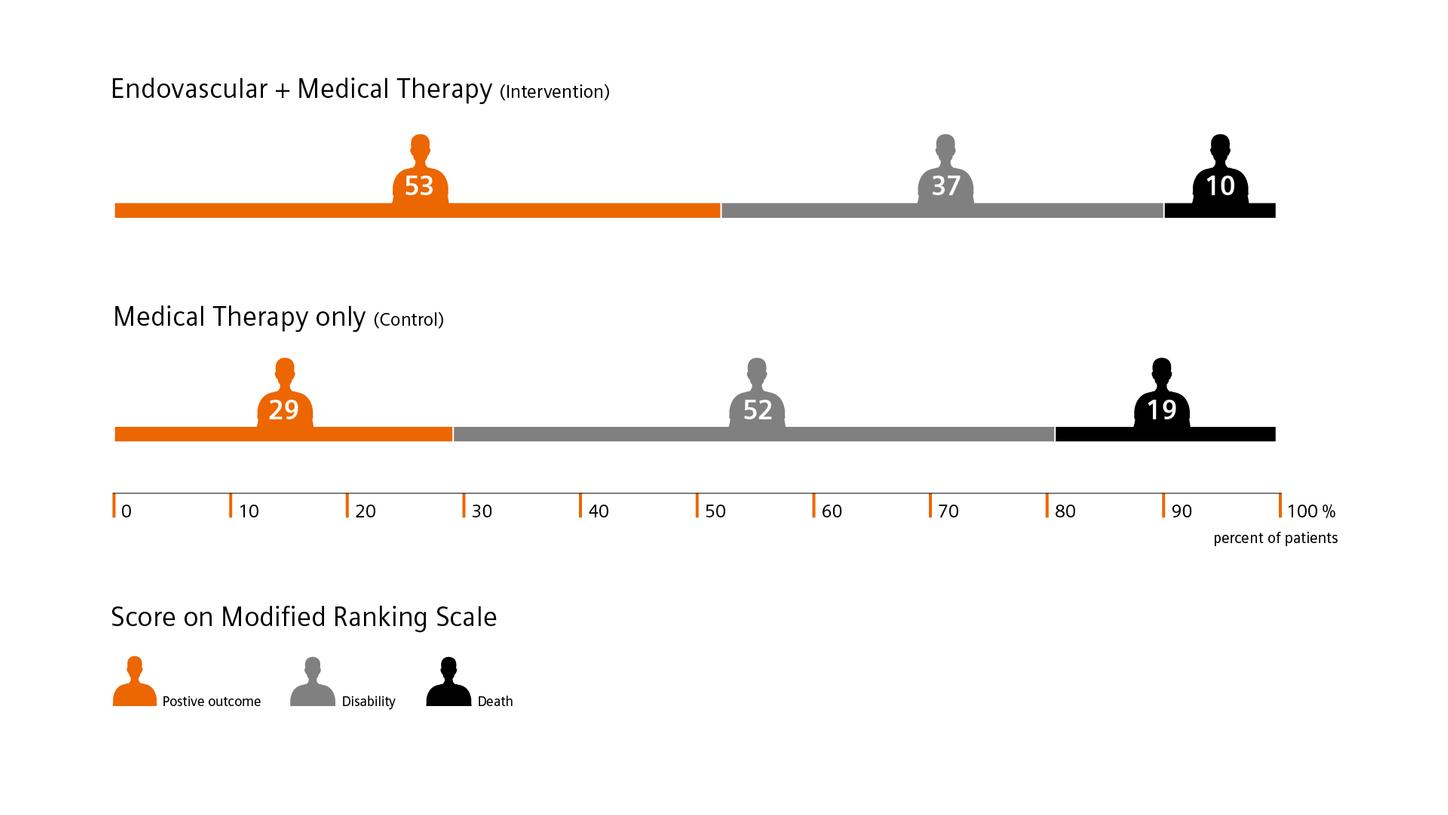

In recent years, various clinical trials have shown the advantages of performing endovascular thrombectomy in patients with a high stroke score as well as of one-stop stroke care.

The DAWN trial shows that time alone shouldn’t be a disqualifier for endovascular thrombectomy. For example: 48.6% of patients in the thrombectomy group experienced less disability, compared to 13% in the control group who received standard medical care.4

DEFUSE 3 shows favorable outcomes for late-window patients. For example: Mortality rate was 14% in the endovascular therapy group, compared to 26% in the medical therapy group. And there was no significant between-group difference in adverse events.4

ESCAPE trial “Among patients with acute ischemic stroke with a proximal vessel occlusion, a small infarct core, and moderate-to-good collateral circulation, rapid endovascular treatment improved functional outcomes and reduced mortality.” (from the publication)5

In their study, M. Psychogios et al. have shown that diagnosing and treating potential LVO patients on one system can save valuable time and significantly improve functional outcome.6

The DAWN trial shows that time alone shouldn’t be a disqualifier for endovascular thrombectomy. For example: 48.6% of patients in the thrombectomy group experienced less disability, compared to 13% in the control group who received standard medical care.4

DEFUSE 3 shows favorable outcomes for late-window patients. For example: Mortality rate was 14% in the endovascular therapy group, compared to 26% in the medical therapy group. And there was no significant between-group difference in adverse events.4

ESCAPE trial “Among patients with acute ischemic stroke with a proximal vessel occlusion, a small infarct core, and moderate-to-good collateral circulation, rapid endovascular treatment improved functional outcomes and reduced mortality.” (from the publication)5

In their study, M. Psychogios et al. have shown that diagnosing and treating potential LVO patients on one system can save valuable time and significantly improve functional outcome.6